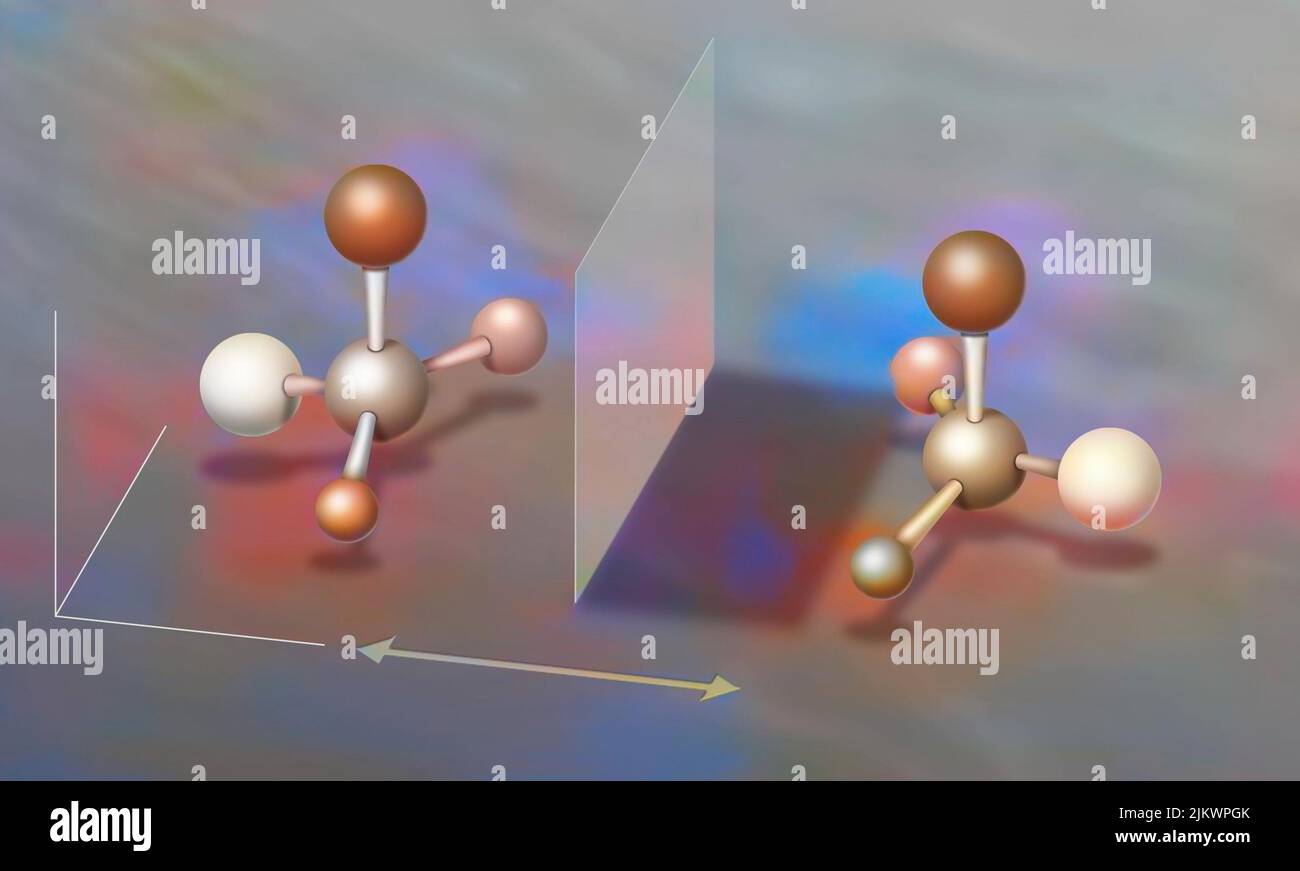

RF2JKWPGK–Acide aminé non synthétisé par la voie du ribosome dont seul l'acide de gauche peut être synthétisé par les ribosomes. C'est pourquoi la synthèse des antibiotiques est si complexe.